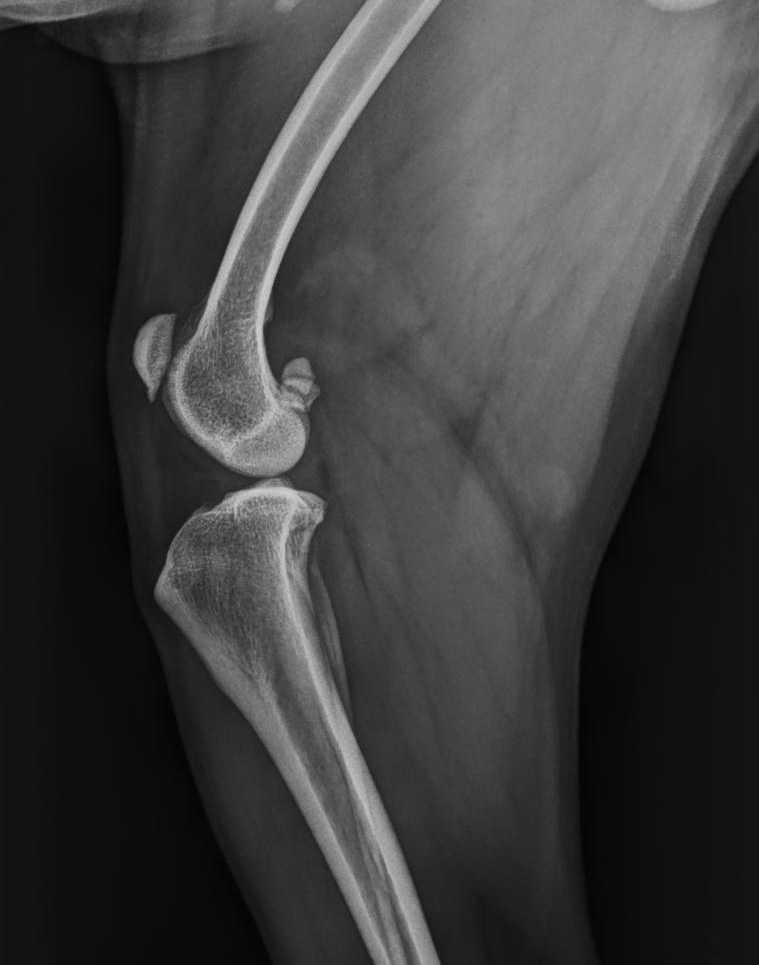

A thorough physical examination and diagnostic imaging are essential for diagnosing patella luxation:

Example of a surgical intervention using a tibial tuberosity transposition technique. Image courtesy of Dr. Luca Petagna.